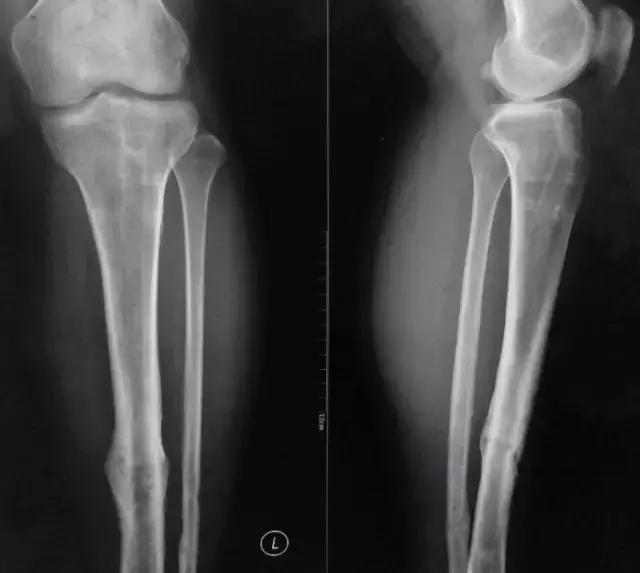

患者男,27岁, 5年前因左腔骨中下段开放骨折入院行交锁髓内钉固定术,切口一期愈合拆线出院。约2年前行内固定取出术,术后恢复良好。2个月前右膝髌韧带切口处时常出现破溃流脓(曾切开未发现线结)。市人民医院分泌物涂片检查示少许白细胞。现诊断疑为骨髓炎?现左小腿无疼痛,无发热,无特殊感觉。

影像检查

诊断:感染。 检查:膝关节MRI,确认伤口窦道是否与髓腔相通。 治疗:1、血沉和C反应蛋白正常,目前无需特殊处理。 2、如果窦道反复出现或血沉和C反应蛋白升高可斟酌手术。如证明窦道与髓腔相通,需行扩髓。

1、诊断:感染。(如果窦口与髓腔相通就是骨感染) 2、检查中血沉和要动态检查。如果局部红肿伴胀痛就查。 3、如果扩髓需要远近端开口。

核磁示中下段骨髓炎,上面切口处流脓,请问张主任你的意见要上手术吗?